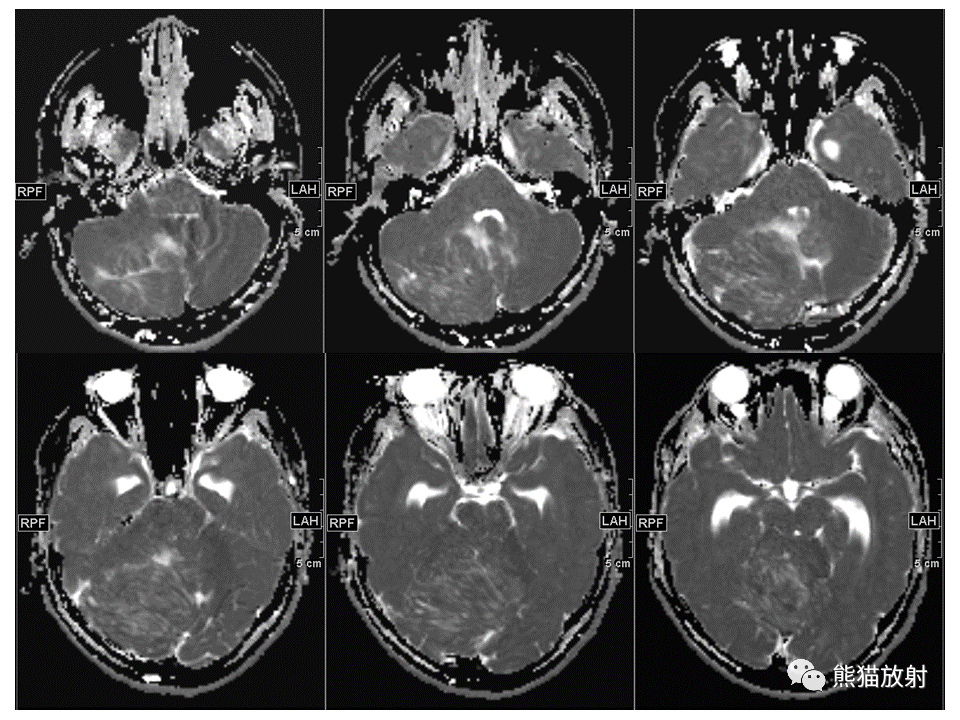

【PPT】小脑发育不良性神经节细胞瘤 VS 成人型髓母细胞瘤-2